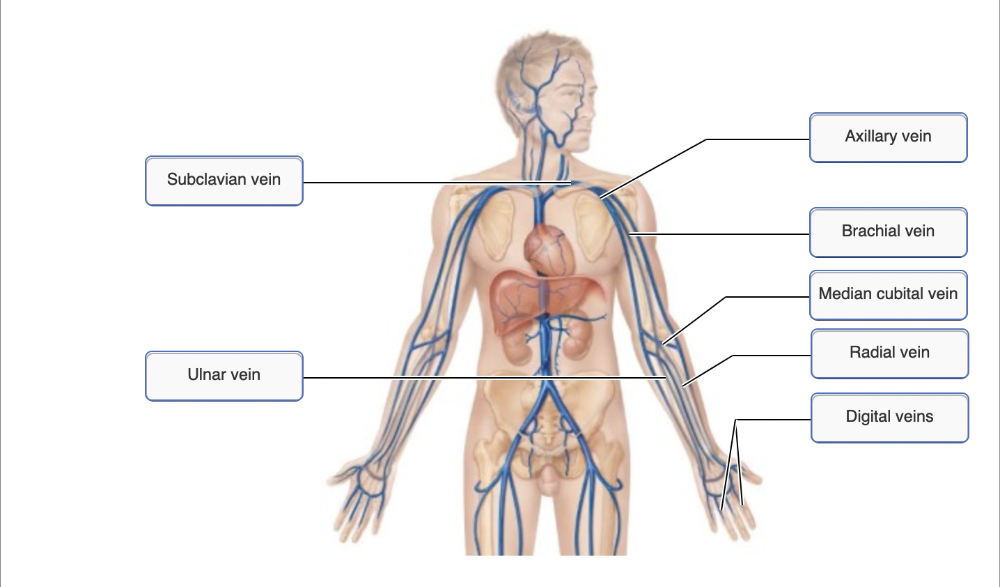

Drag the appropriate labels to their respective targets.